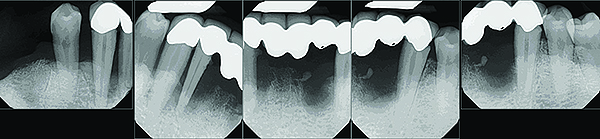

The bone destruction patterns that occur as a result of periodontal disease generally take on characteristic forms This Xray film displays a horizontal defect This Xray film displays two lonestanding mandibular teeth, #21 and #22 the lower left first premolar and canine, exhibiting severe bone loss of 3050%Osseous or Bony defects Any concavity or deformity in the alveolar bone that represents a change from normal contour as a result of periodontal disease EX craters, vertical defects (1 wall, 2 wall, 3 wall), hemiseptal, circumferential (moat)As 3D printing technology emerge, there is increasing demand for a more customizable implant in the repair of chestwall bony defects This article aims to present a custom design and fabrication method for repairing bony defects of the chest wall following tumour resection, which utilizes threedimensional (3D) printing and rapidprototyping technology

The bone destruction patterns that occur as a result of periodontal disease generally take on characteristic forms This Xray film displays a horizontal defect This Xray film displays two lonestanding mandibular teeth, #21 and #22 the lower left first premolar and canine, exhibiting severe bone loss of 3050%Molar teeth with three or more bony wall defects are most commonly lost if timely intervention is not done Etiology of intrabony defect involvement includes local environmental factors such as tooth position which contributes to food impaction, plaque accumulation, angular position, or position of the tooth with respect to the alveolarCase 2 A wide 3wall intrabony defect on the distal aspect of tooth #30 This defect was regenerated successfully using autogenous bone harvested from the adjacent edentulous ridge in combination